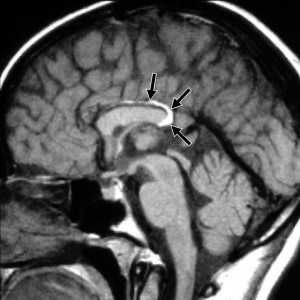

Нейроглиальная киста

Нейроглиальная киста (син. глиоэпендимальная киста, нейроэпителиальная киста) - это редкое доброкачественное кистозное образование центральной нервной системы выстланное эпителием. При визуализации представляет собой округлое образование с гладкими ровными контурами, с содержимым соответствующим по характеристикам спинномозговой жидкости, с минимальными изменениями окружающей ткани [1].

Нейроглиальные кисты являются врожденными образованиями располагающимися в белом веществе, они образуются за счет секвестрации элементов нервной трубки в эмбриональном периоде с формированием заполненной жидкостью полости выстланной глиальными клетками [3].

Обычно представляют собой четко отграниченные не усиливающиеся гиподенсивные образования с плотностью соответствующей плотности спинномозговой жидкости, как правило единичные, без перифокального отека, кальцинатов или признаков объемного воздействия.

Нейроглиальные кисты по сигнальным характеристиками соответствуют спинномозговой жидкости, и имеют гипоинтенсивный сигнал на Т1 изображениях, и гиперинтенсивный сигнал на Т2 изображениях, как правильно с подавлением сигнала на FLAIR последовательностях.